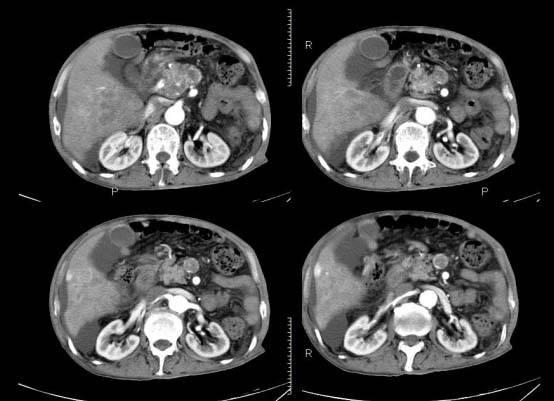

以下是引用杀毒软件在2010-3-30 18:11:00的发言:[br]考虑---hcc侵犯侵犯周围组织〔胰腺、胆管、肠系膜上动静脉〕伴门脉、下腔静脉癌栓形成、动-静脉瘘、肝门、腹腔动脉周围淋巴结转移可能性大、腹水。

以下是引用pujunzhi在2010-3-31 8:45:00的发言:[br]支持 肝癌并多发肝内转移,胰头、肝门、腹腔动脉周围淋巴结转移,下腔静脉癌栓形成,肝硬化、腹水。

以下是引用jsgdoctor在2010-3-30 20:42:00的发言:[br]考虑---hcc侵犯侵犯周围组织〔胰腺、胆管、肠系膜上动静脉〕伴门脉、下腔静脉癌栓形成、动-静脉瘘、肝门、腹腔动脉周围淋巴结转移可能性大、腹水。